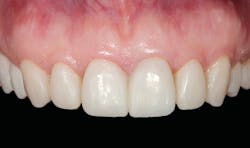

A patient presented with multiple deficient restorations, discolored teeth, and attrition (figures 1–4). The patient’s treatment plan was a full-mouth rehabilitation with a combination of veneers, crowns, and onlays.

Esthetic and functional prototypes are an effective way to evaluate esthetics and function of a proposed restorative plan, all while spreading the cost of definitive treatment over time. Esthetic, functional, and long-lasting restorations can be achieved if clinical and laboratory protocols are carefully followed using adhesive additive techniques.